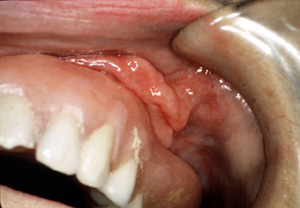

| El épulis

fisurado representa una masa hiperplásica de la mucosa, generalmente en

el vestíbulo de la boca, proliferando como una reacción a la

irritación mecánica de largo

plazo de una prótesis dental mucosoportada mal adaptada.

Aquí son

dos épulis, bilaterales, en los vestíbulos del maxilar. Es una

apariencia típica. Son lobulados y

muestran áreas focales aumentadas de vascularidad. En la porción

central de cada masa hay una ranura ó una invaginación

que corre en una dirección anterior-posterior. La pestaña de la

dentadura postiza encajará en estas ranuras.

| Esta vista más

aumentada de la lesión del lado izquierdo

está compuesta de por lo menos tres pliegues de tejido bastante

denso. Hay invaginaciones profundas entre los pliegues.